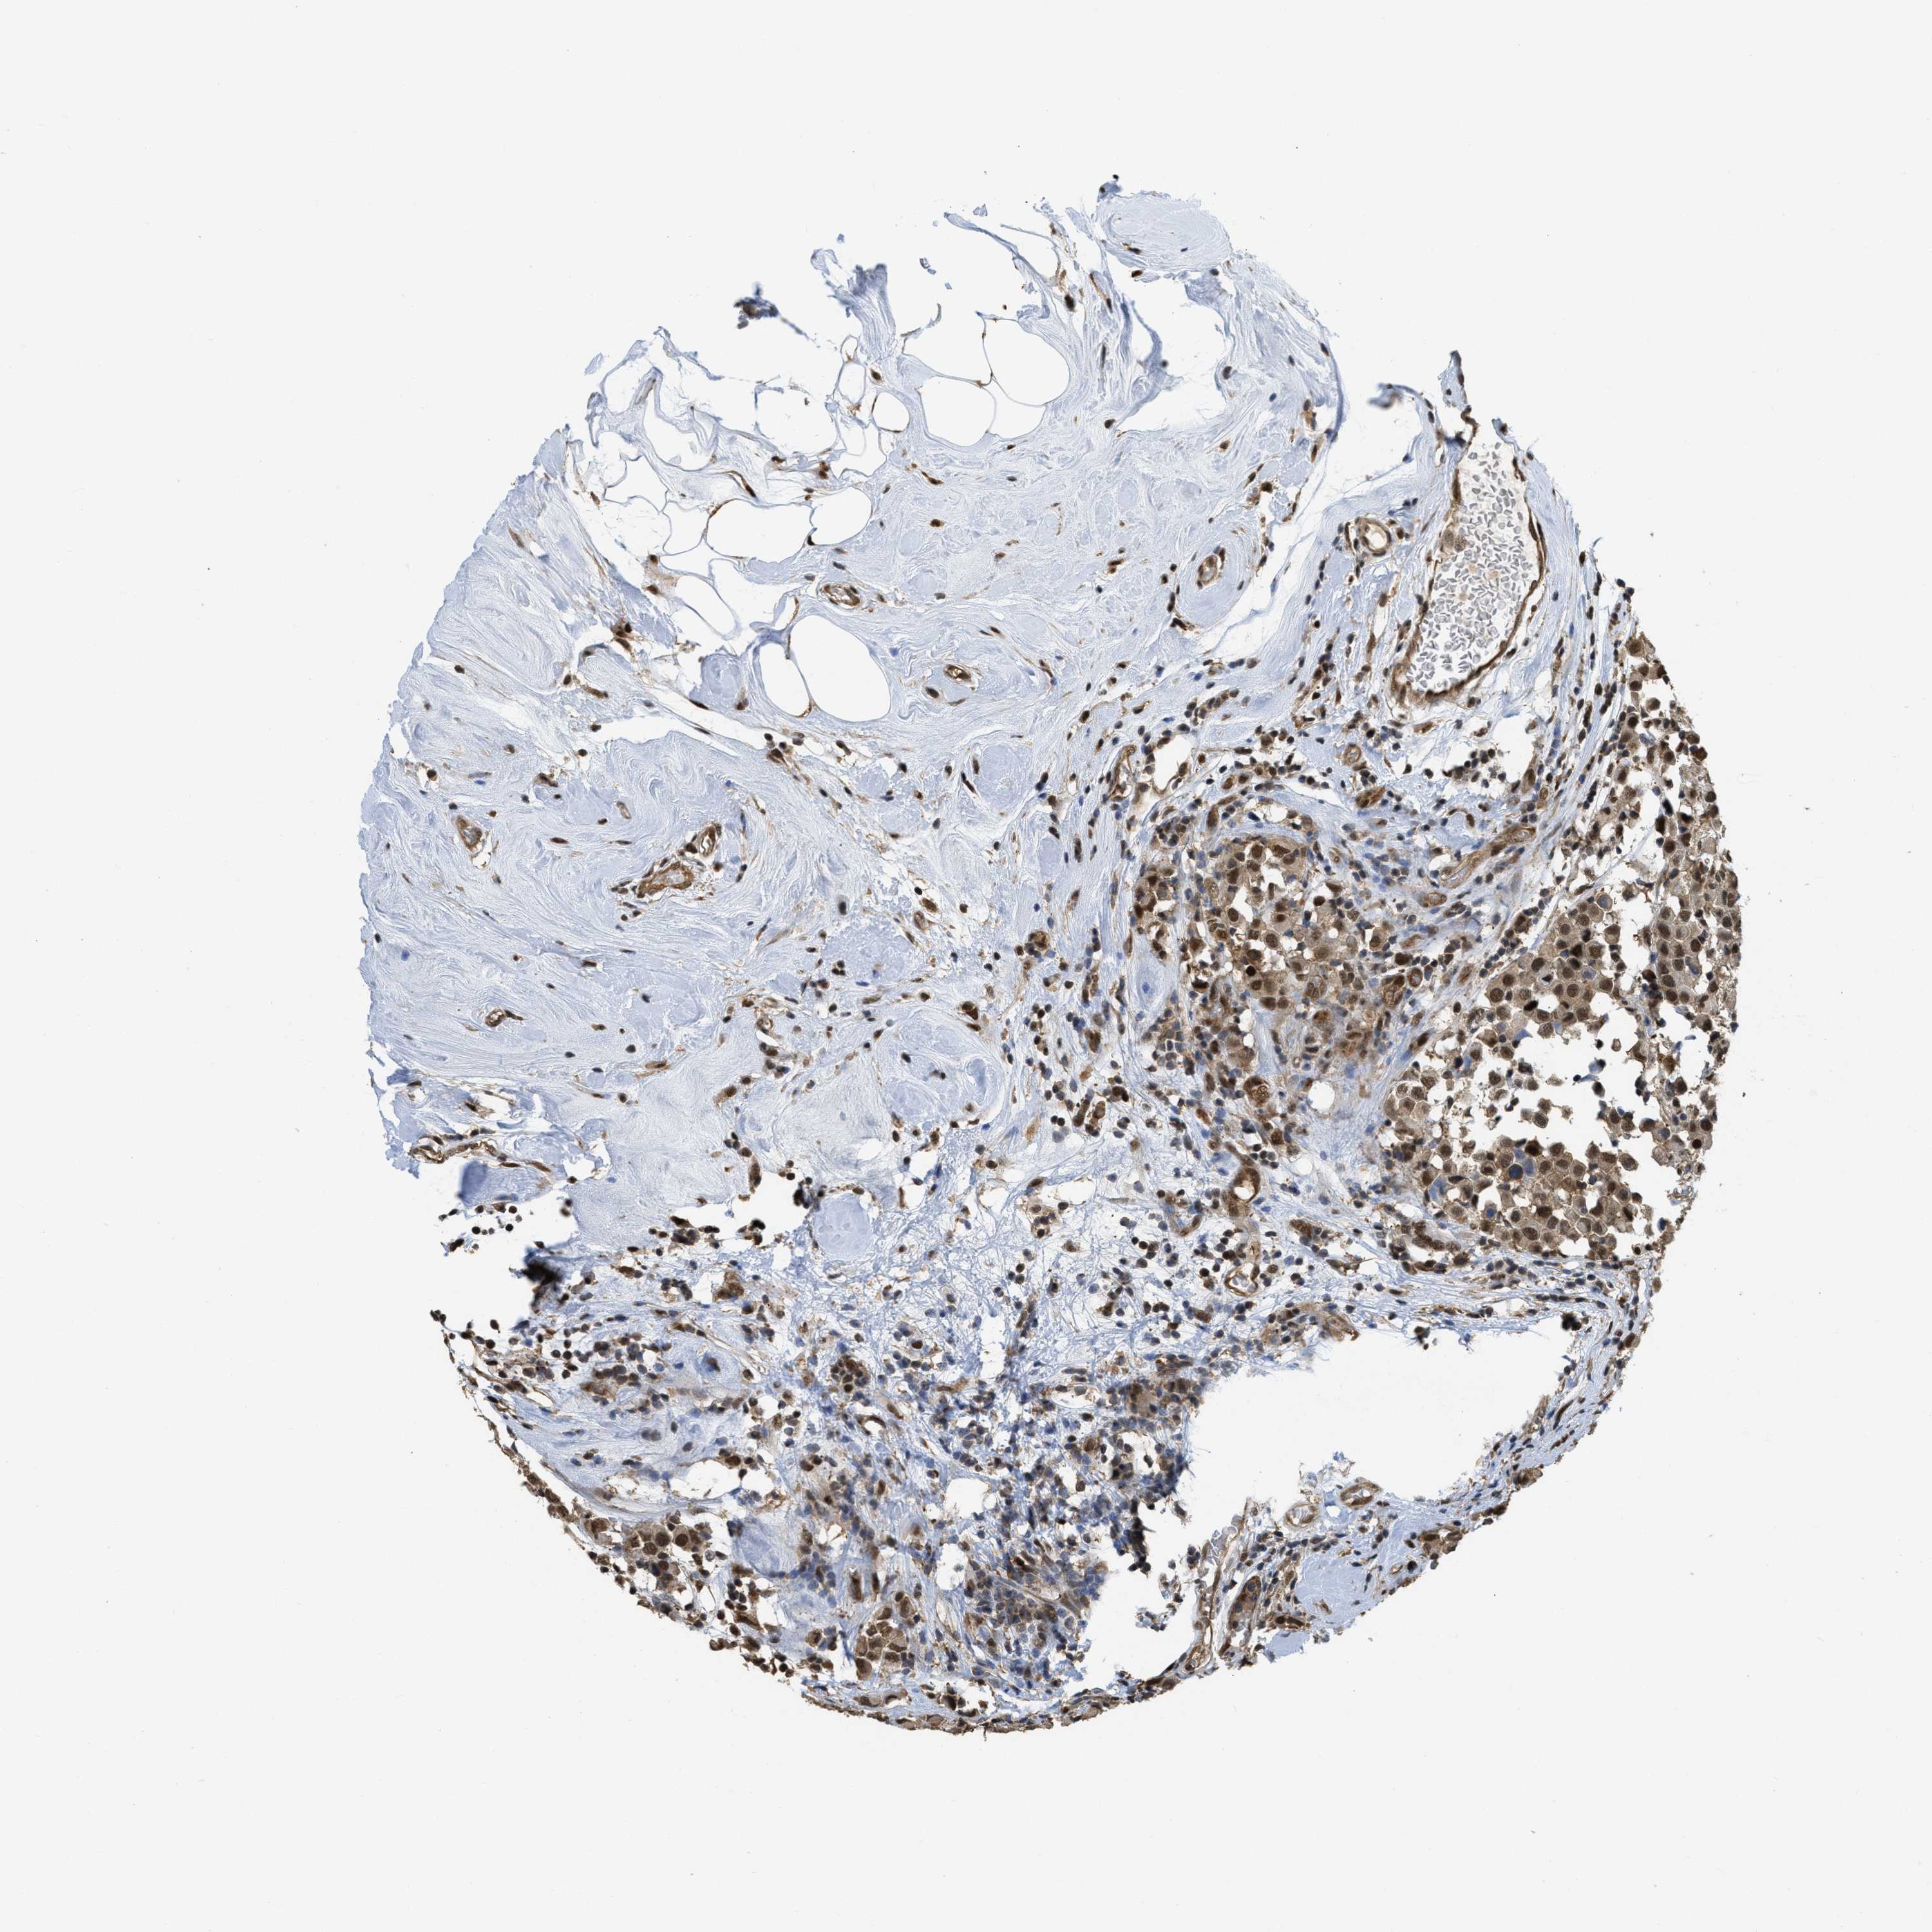

CANCER BREAST CANCER Show tissue menu

BRCA TCGA BRCA VALIDATION PROTEIN EXPRESSION